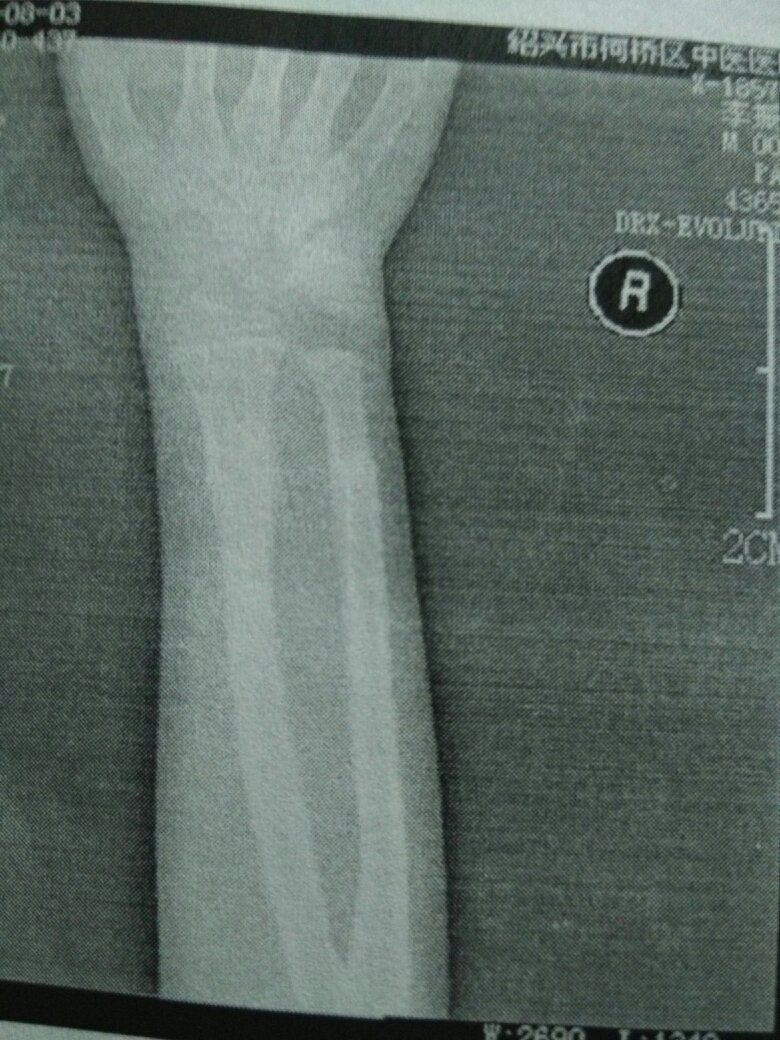

右手桡尺骨骨折保守治疗现在骨头有点弯以后会有影响吗孩子八岁 点击展开 匿名用户 2015-08-07 14:07 满意回答 你好,寸细富病情分析,右手桡尺骨骨折保守治疗,现在骨头有径梅点弯,考虑概究以后不会有影响 cn#BppakBVVfa 2015-08-07 14:32 宝宝知道提示您:回答为网友贡献,仅供参考。 相关问题 小孩右手弯骨折好了以后有一个小骨头包会不会对小孩身长发育有影响 我盆骨去年十一月份粉碎骨折保守治疗,现在验出怀孕,这孩子能不能要呢? 我妹妹去产检医生说过了预产期,孩子偏大,骨头长硬了,顺产的话婴儿会骨折,是真的吗?!